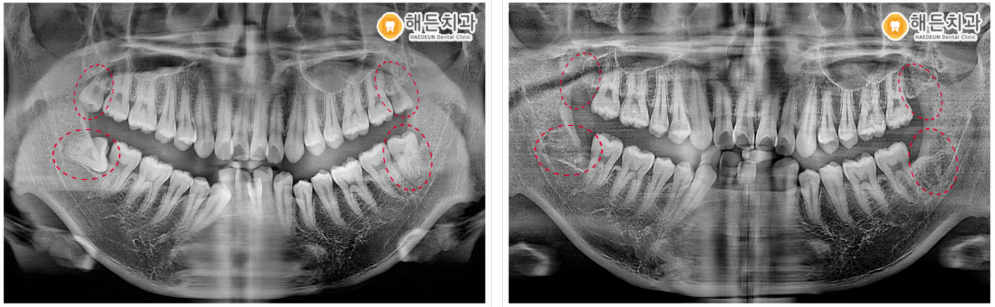

저희 천안아산치과 해든에서는 풍부한 사랑니 발치 노하우를 갖고 있는 대표 원장님께서 발치 전 CT 촬영을 통해 사랑니의 위치, 신경과의 거리, 인접 구조물과의 거리 등을 정밀하고 꼼꼼하게 체크한 후에 안정적으로 발치를 진행하였습니다!

4개 모두 남은 뿌리 없이 깔끔하게 사랑니발치를 도와드렸습니다. ✌

🦷 전 >후 🦷